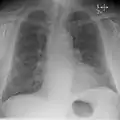

Chest X-rays are frequently used to aid in the diagnosis of CHF. In a person who is compensated, this may show cardiomegaly (visible enlargement of the heart), quantified as the cardiothoracic ratio (proportion of the heart size to the chest). In left ventricular failure, evidence may exist of vascular redistribution (upper lobe blood diversion or cephalization), Kerley lines, cuffing of the areas around the bronchi, and interstitial edema. Ultrasound of the lung may also be able to detect Kerley lines.[69]

Congestive heart failure with small bilateral effusions